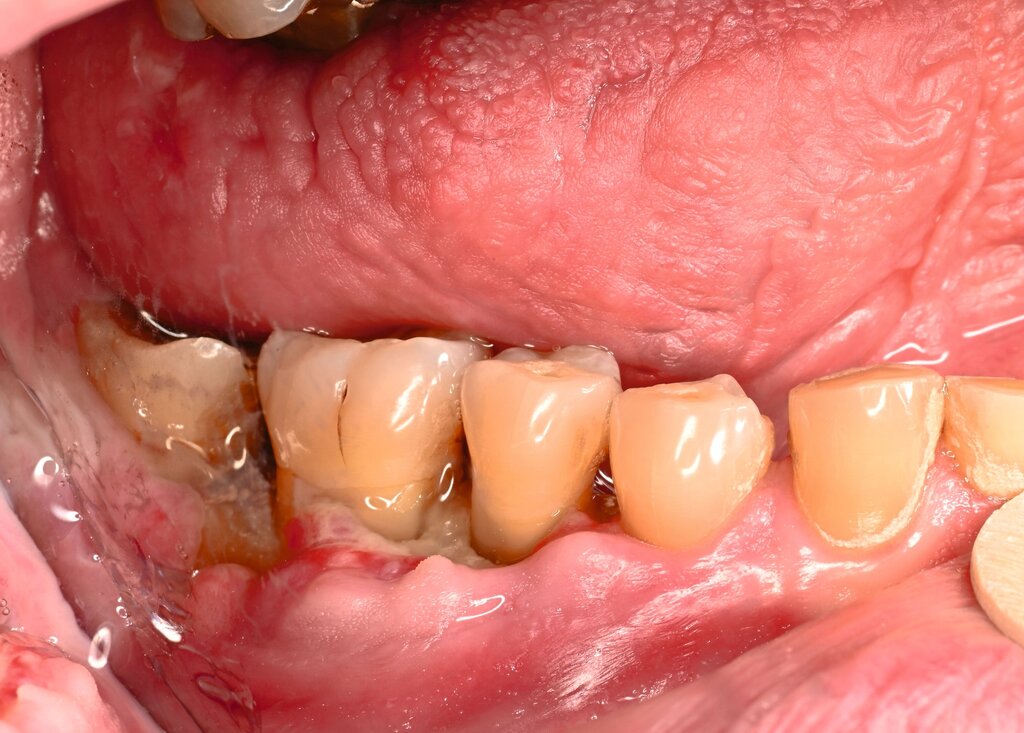

Der Patient stellte sich mit freiliegendem Knochen in Regio 43 bis 47 und mehreren gelockerten Zähnen vor. 45 und 46 waren devital. Als klinische Besonderheit fiel auf, dass sich innerhalb der Nekrosezone kleinflächige Weichgewebsareale darstellten, die in dieser Form bei klassischen Osteonekrosen üblicherweise nicht beobachtet werden. Eine klassische Vincent-Symptomatik bestand nicht. Drei Wochen zuvor war eine Herpes-Zoster-Infektion dermatologisch diagnostiziert und zunächst stationär behandelt worden. Der Patient erhielt eine intravenöse, antivirale Therapie, die bei Entlassung oralisiert wurde.

In den publizierten Fallserien war der Unterkiefer häufiger betroffen als der Oberkiefer (Verhältnis etwa 3,5 zu 1). Der Krankheitsbeginn liegt meist zwischen der zweiten und der vierten Woche nach den Hauteffloreszenzen, kann aber auch verzögert auftreten [Mintz, 1992; Badjate, 2009]. Typisch ist ein einseitiger Verlauf entlang der betroffenen Nervenäste, auch mit spontaner Zahnexfoliation, freiliegendem Knochen und (manchmal) persistierender Neuralgie. Differenzialdiagnostisch müssen die MRONJ, die Osteoradionekrose und die bakterielle Osteomyelitis ausgeschlossen werden. Wenn diese Ursachen fehlen und eine zeitlich assoziierte Herpes-Zoster-Infektion besteht, ist die Diagnose einer HZ-assoziierten Osteonekrose naheliegend [Aghaloo, 2017].

Die Prognose der HZ-ONJ ist in der Regel gut, wenn eine adäquate antivirale Therapie erfolgt und nekrotisches Gewebe entfernt wird. Langzeitverläufe zeigen stabile Verhältnisse ohne Rezidiv [Chen, 2019; Chatterjee, 2023]. Entscheidend ist eine frühzeitige und auch kontinuierliche zahnärztliche Begleitung bei Herpes-Zoster-Infektionen des Nervus trigeminus, da dentoalveoläre Komplikationen auch Wochen nach dem initialen Hautbefall auftreten können [Huang, 2024]. Eine enge interdisziplinäre Zusammenarbeit zwischen Dermatologie, Zahnmedizin und Mund-, Kiefer- und Gesichtschirurgie ist daher unabdingbar.